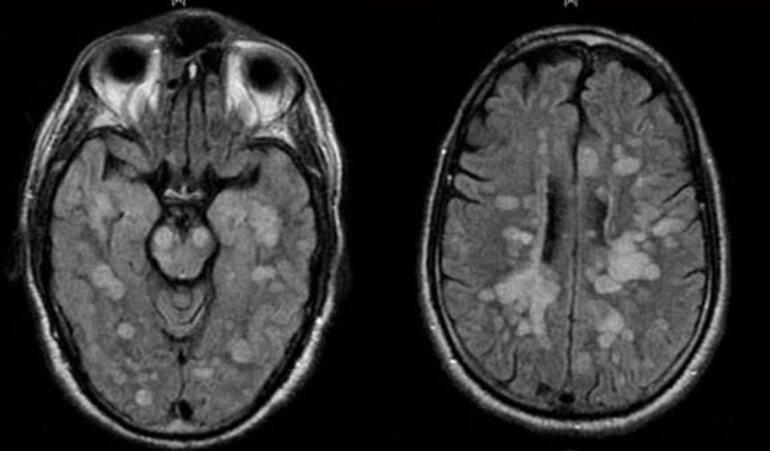

Talihsiz çocuğa vücudun bağışıklık sistemi kendisine saldırarak omurilik ve beynin şişmesine neden olan nadir bir akut yayılmış Ensefalit (ADEM) teşhisi koyuldu.